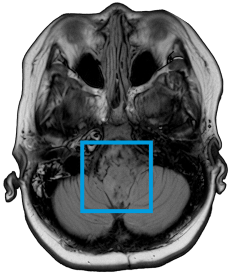

The first and only type II RAF inhibitor for BRAF alterations in relapsed or refractory pediatric low-grade glioma (R/R pLGG)1

OJEMDATM (tovorafenib) is indicated for the treatment of patients 6 months of age and older with relapsed or refractory pediatric low-grade glioma (LGG) harboring a BRAF fusion or rearrangement, or BRAF V600 mutation.